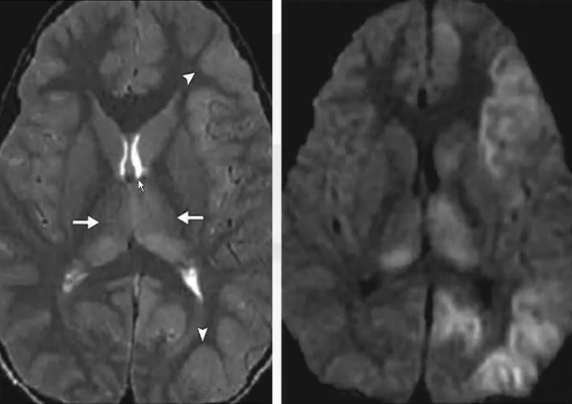

❖ 乙型脑炎常累及双侧丘脑,主要表现为双侧丘脑-基底节和(或)其他脑叶内的多发CT低密度影及MRI异常信号影,皮层下病灶容易合并出血,其中双侧丘脑合并基底节对称性低密度影或异常信号影比较有特异性。